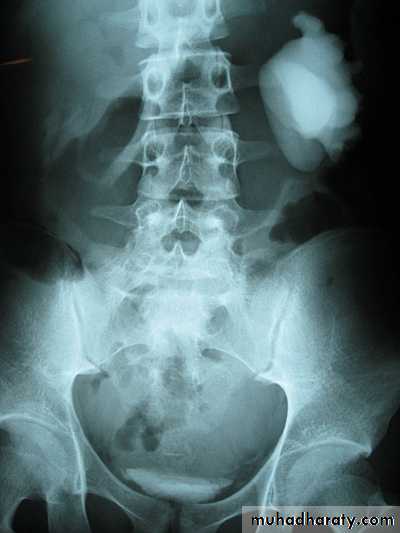

Horse shoe kidney -Kidneys may fail to separate.

-Almost invariably the lower poles remain fused.

-The kidneys axes are more parallel to the spine and malrotated.

-Diagnosis can be made by plain x-ray in some cases.

-US, CT scan and MRI can better demonstrate the anatomy and morphology hence the diagnosis.

-May be an incidental finding.

-PUJ obstruction and calculi formation are common .

IVU shows

1. The kidneys at low position .

2.Close to the spine with long axis parallel to the spine .

3. Malrotation manifested by medially directed calyces.

4- The renal pelvis and ureters are anterior and lateral in position .